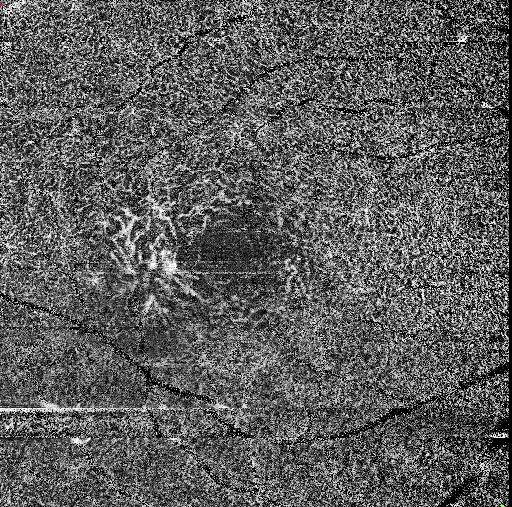

On optical coherence tomography angiography (OCTA), the superficial capillary plexus typically shows mild capillary rarefaction with dilated and right-angled venules, predominantly in the temporal parafoveal region.

The deep capillary plexus demonstrates more pronounced abnormalities, including telangiectatic and ectatic vessels, capillary dropout, and disorganization of the vascular network, which represent the hallmark vascular changes of MacTel type 2.

In the avascular (outer retinal) slab, the presence of a pathologic flow signal indicates subretinal neovascularization, appearing as a tangled, irregular vascular complex extending from the deep plexus into the outer retina. This neovascular network is often better delineated on OCTA than on conventional angiography and correlates with exudative changes observed on structural OCT.